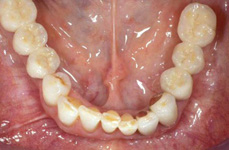

V případě chybění většího počtu zubů v postranních úsecích čelistí je možné ošetření pomocí implantátů, které nahradí ošetření pomocí snímacích náhrad kotvených na zbývajících zubech nebo patře.

Podmínkou je opět dostatečné množství kosti.

Protetické řešení může být pomocí můstku, který je kotvený na implantátech nebo pomocí jednotlivých korunek na implantátech.

V zásadě je možné do těchto můstků zařadit i přirozené zuby, zejména pokud je potřeba tyto zuby ošetřit proteticky

- korunkami. Korunky nebo můstky mohou být na implantáty nacementovány nebo přišroubovány.

Zdravé zuby zůstanou zachovány a přitom náhrady jsou pevné, jako na vlastních zubech